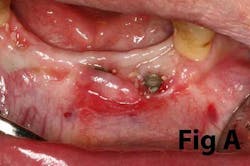

Case No. 1